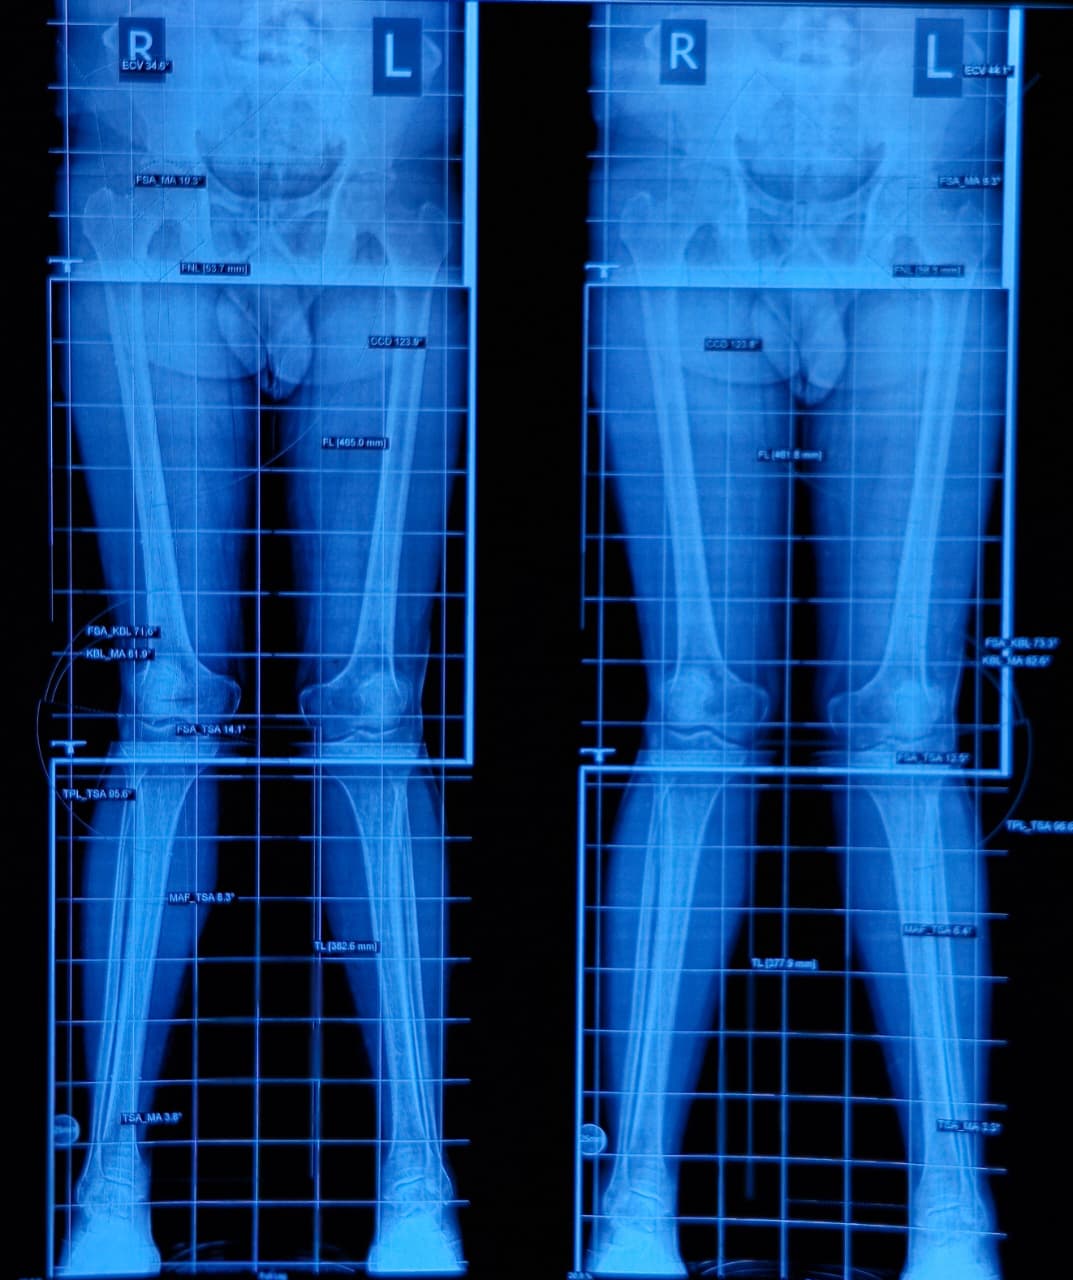

Bow legs, also known as genu varum, is a condition where the legs appear bowed outwards when standing. This condition can cause discomfort, pain, and even difficulty walking. In severe cases, surgery may be required to correct the alignment of the legs. In this article, we will discuss the causes, symptoms, and treatment options for bow legs, including the various surgical procedures available.

A doctor can diagnose bow legs by performing a physical examination and assessing the alignment of the legs. Imaging tests such as X-rays or MRI scans may also be used to confirm the diagnosis.